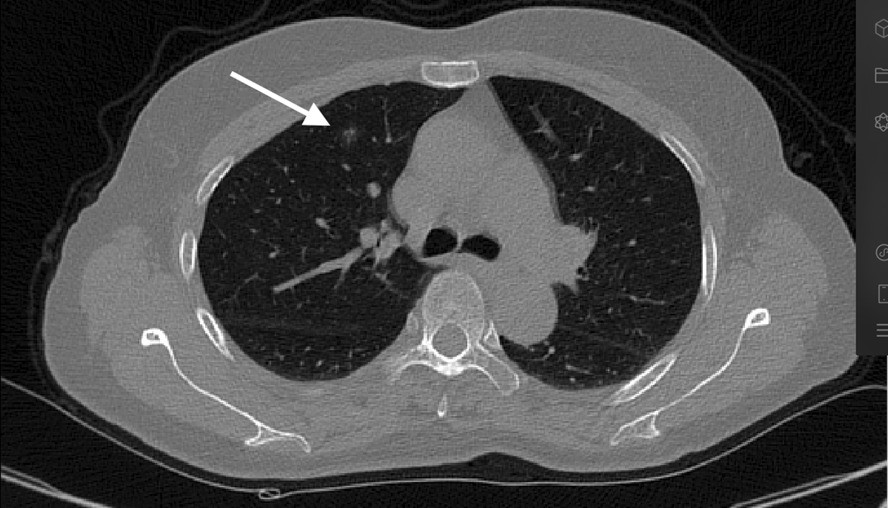

Fig. 3From: Application of three-dimensional reconstruction combined with dial positioning in small pulmonary nodules surgeryRotate the plane, so that the affected side is upwardBack to article page